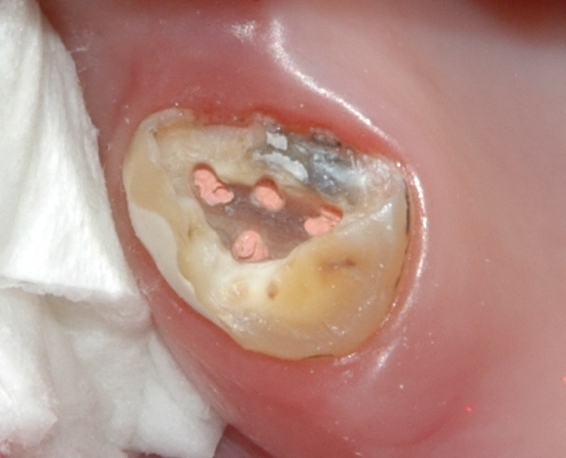

Zub se čtyřmi zaplněnými kořenovými kanálky